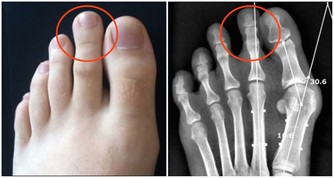

供應部位:生殖器官、子宮、膀胱、膝;神經受壓後果:膀胱病、月經不調、小產、膝痛